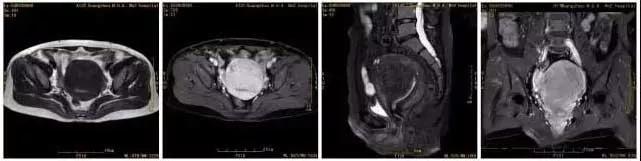

王女士 术前MRI显示子宫肌瘤大小约9cmX7cm

王女士术后MRI显示原病灶明显坏死、缩小,大小约5cmX4cm,随着时间的延长病灶将进一步缩小。